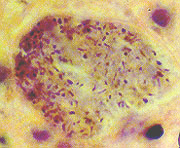

Plasmodium sp: schizont